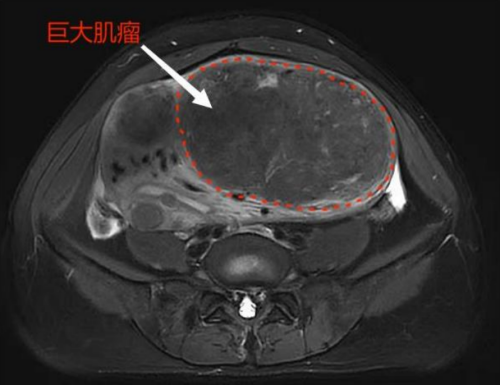

刘爱娇入院后,接诊的妇科主任医师曹荣花对她进行了详细的病史询问及查体。原来今年50岁的刘爱娇,在十年前体检时就发现了子宫肌瘤,当时医生嘱咐其定期复查。因当时肌瘤较小,直径不到2厘米,且身体没有任何不适症状,刘爱娇也就没当回事,也没有按医生的要求定期复查。这次检查时发现,刘爱娇的腹部隆起,子宫明显增大,子宫底部已达脐部上方,俨然如怀孕6月左右大小。妇产科一区医生为其进一步完善了核磁共振检查,结果显示刘爱娇子宫内有多发肌瘤。

经过充分的术前讨论,结合刘爱娇年龄及意愿,黄佼副主任及其医疗团队为刘爱娇完成了子宫切除手术。术中见子宫多发肌瘤,其中有两个较大的肌瘤直径约15cm、12cm。刘爱娇表示,原以为是中年发福,没想到自己子宫里会长出这么大的肌瘤,非常感谢妇产科一区的医护团队帮她卸下了这个“大包袱”。